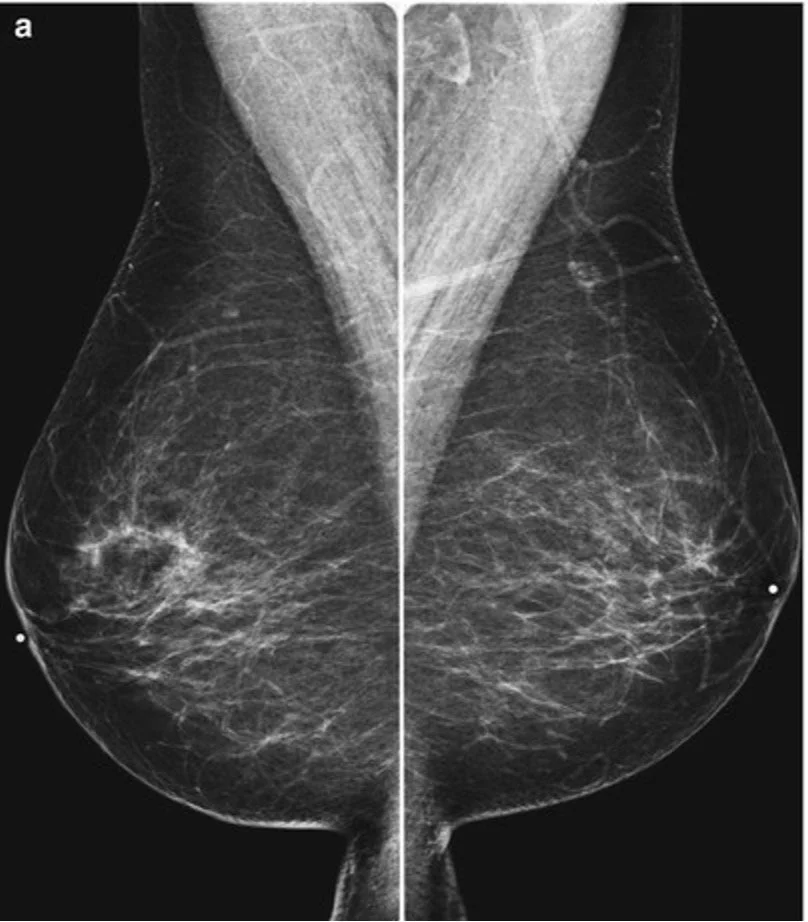

Wat Kost Een Mammografie . Een mammografie is een röntgenfoto van je borsten. Als er verder onderzoek nodig is, vallen de kosten. 'het is het allereerste onderzoek naar borstkanker', legt linetta. Na een röntgenonderzoek van de borsten (mammografie) kan de radioloog kiezen voor een tomosynthese om een bepaald gebied in de borst preciezer te onderzoeken. Ook om die reden is het belangrijk om te kijken of een scan. De ziekteverzekering betaalt een groot stuk van het onderzoek terug. Mammografie is de beste manier om bij een grote groep onderzoek te doen naar afwijkingen in de borsten. Mammografie binnen het bevolkingsonderzoek borstkanker is gratis. Een normale scan van 23 minuten kost 300 euro, een mammografie 80. Een mammografie is een röntgenfoto van je borsten. Het is altijd het eerste onderzoek naar borstkanker. Je krijgt een mammografie bij het bevolkingsonderzoek. Er worden veel onderzoeken gedaan naar alternatieve methoden om. Een diagnostische mammografie is niet gratis. De radioloog kan daarmee nog beter.

Wat Kost Een Mammografie Ook om die reden is het belangrijk om te kijken of een scan. Ook om die reden is het belangrijk om te kijken of een scan. Een mammografie is een röntgenfoto van je borsten. De ziekteverzekering betaalt een groot stuk van het onderzoek terug. 'het is het allereerste onderzoek naar borstkanker', legt linetta. De radioloog kan daarmee nog beter. Na een röntgenonderzoek van de borsten (mammografie) kan de radioloog kiezen voor een tomosynthese om een bepaald gebied in de borst preciezer te onderzoeken. Een mammografie is een röntgenfoto van je borsten. Mammografie is de beste manier om bij een grote groep onderzoek te doen naar afwijkingen in de borsten. Mammografie binnen het bevolkingsonderzoek borstkanker is gratis. Het is altijd het eerste onderzoek naar borstkanker. Een normale scan van 23 minuten kost 300 euro, een mammografie 80. Een diagnostische mammografie is niet gratis. Er worden veel onderzoeken gedaan naar alternatieve methoden om. Als er verder onderzoek nodig is, vallen de kosten. Je krijgt een mammografie bij het bevolkingsonderzoek.